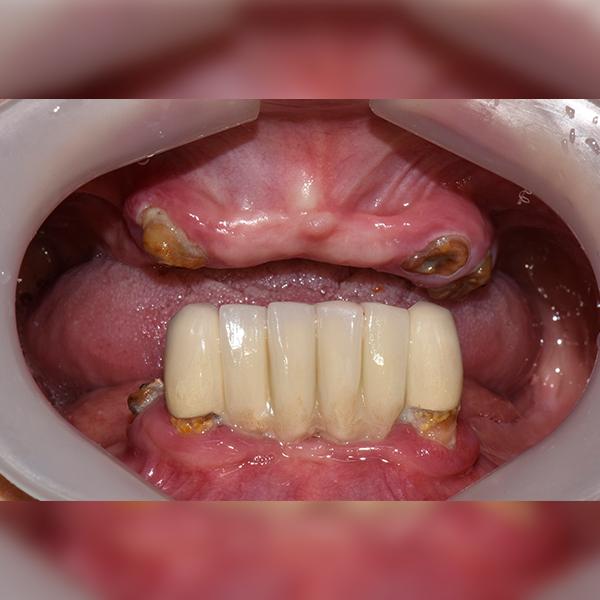

全顎/全体 / 骨移植|睡眠|糖尿病

症例.68 60代 ハン*ブン 2018-05-03 / 2018-11-26